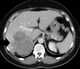

Invasion from adjacent neoplasm

Carcinoma is a malignancy that develops from epithelial cells. Specifically, a carcinoma is a cancer that begins in a tissue that lines the inner or outer surfaces of the body, and that arises from cells originating in the endodermal, mesodermal or ectodermal germ layer during embryogenesis.Carcinomas occur when the DNA of a cell is damaged or altered and the cell begins to grow uncontrollably and become malignant. [Source: Wikipedia ]